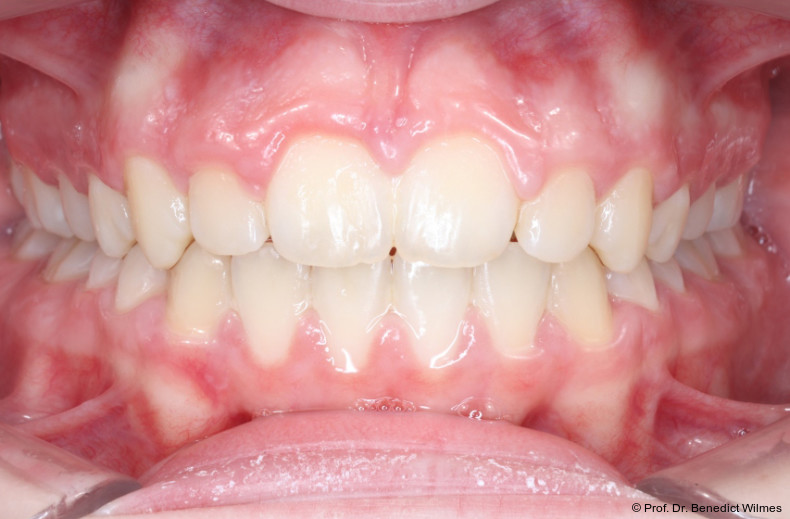

Nach erfolgreicher Expansion und Molaren­intrusion wurde eine Multibracket-Therapie zur Ausformung und Koordination der Zahnbögen durchgeführt (Abb. 8a–f). Nach Abschluss der aktiven Behandlungsphase wurden die Apparaturen entfernt und festsitzende Retainer im Ober- und Unterkiefer eingesetzt (Abb. 9a–k).